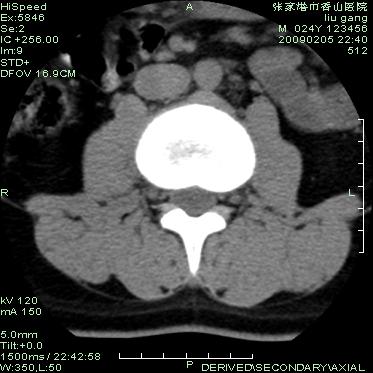

以下是引用随光逐影在2009-3-11 14:43:00的发言:[br]平片:l3、4、5及s1前上缘见类似“切角征”。[br]ct扫描:腰椎多个节段椎间盘向椎体内(椎体前部)突出。